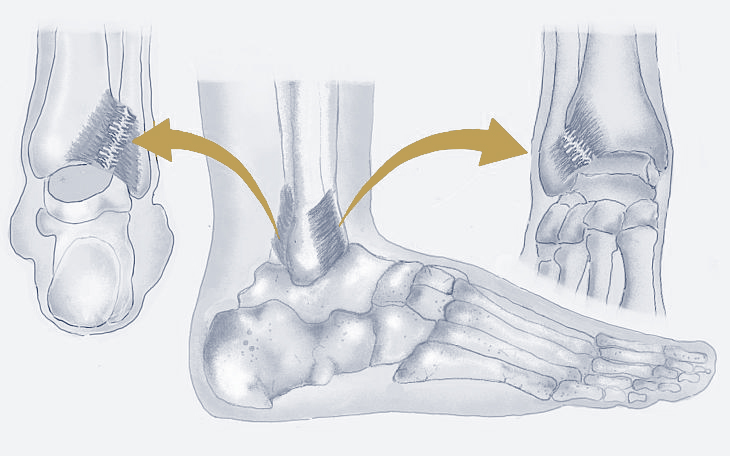

Bildquelle: www.docset.de